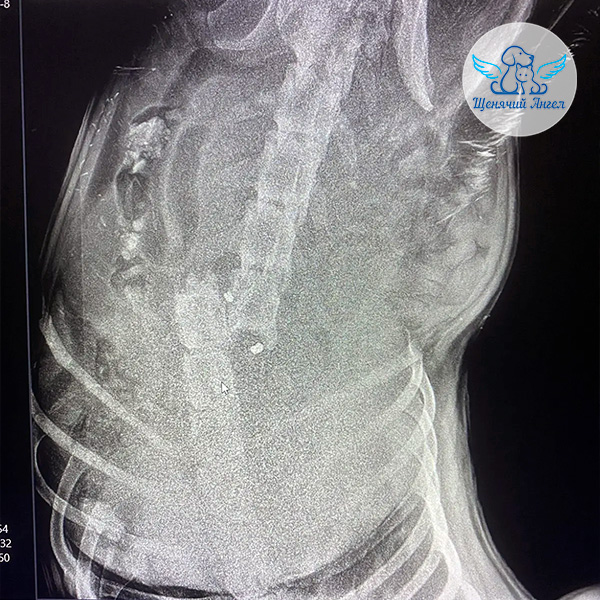

Первичная диагностика и рентген показали перелом позвоночника.

🩻 Рентген подтвердил застарелый перелом позвоночного столба со значительным смещением.

С учётом характера повреждения врачи с высокой вероятностью предполагают разрыв спинного мозга.

Также у Хрома обнаружены инородные предметы – пули: одна в зоне перелома позвоночника, другая в мягких тканях подколенной области 😔

Диагностирована 5 степень неврологического дефицита тазовых конечностей – полное отсутствие глубокой болевой чувствительности.